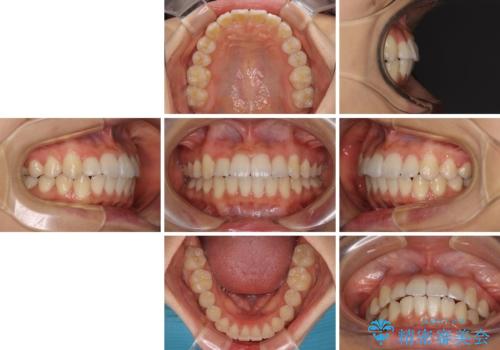

- 上下のデコボコと前歯のクロスバイトを改善したいとのことで来院された患者様です。

極力短期間で治療したいとのことで、ワイヤー装置による矯正治療を行うこととしました。

お住まいが遠方であったため、マウスピースによる矯正治療も提案しましたが、ご自身でのマウスピースの管理の面倒くささと、なるべく早く治療を終えたいとのことで、ワイヤー矯正を選択されました。